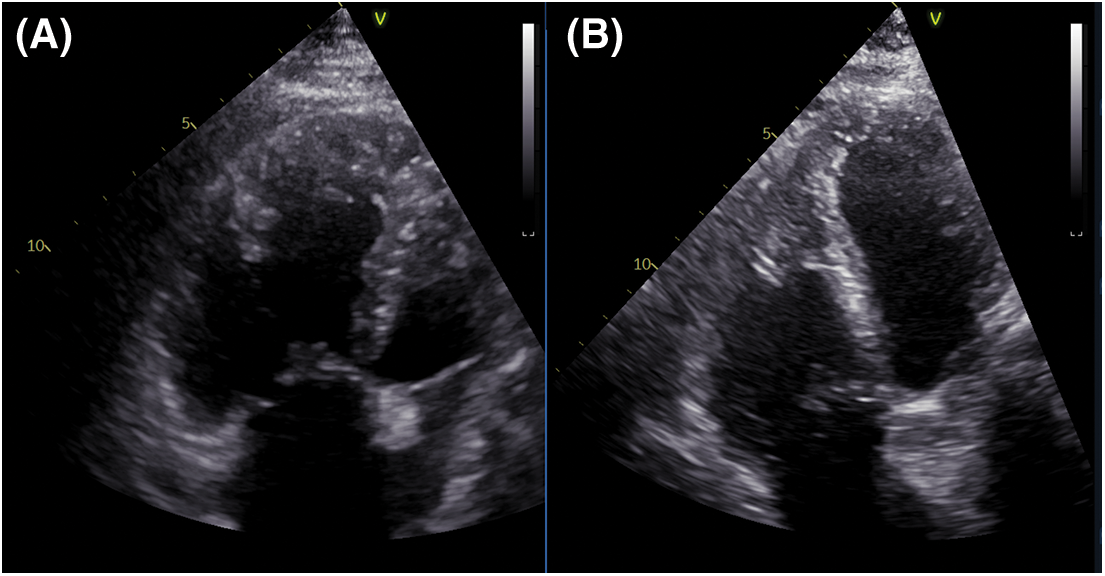

PAH-specific dual therapy was continued postoperatively. After three months, exercise tolerance significantly improved, there was no residual shunt, reverse remodeling of the right ventricle had occurred (Fig. 4), PA diameter was 33 mm. An invasive reassessment found PAPs = 54 mmHg, PAPm = 35 mmHg, PVR = 3.3 WU, and a non-significant LM residual stenosis (30%) (Fig. 1B).

Figure 4: RV remodeling demonstrated by TTE (A) Preoperative exam shows a dilated RV. (B) Three months postoperatively, the TTE revealed significant revers-remodeling of the RV